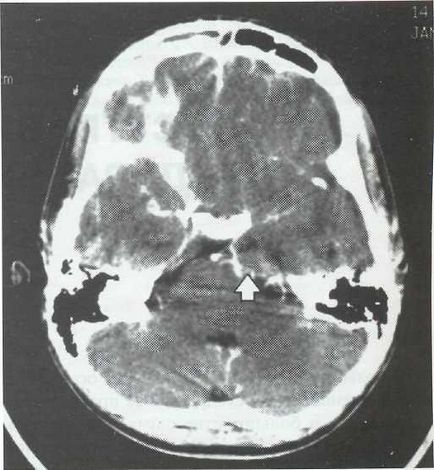

EDS diagnózist CT vagy MRI. Amikor CT EDS látható, ahol a zóna csökkentett félgömb alakú plotnos-ti (ábra. 22-1). Edges gennyes felhalmozódást egyértelműen konturiruyutsya felerősített jel beadva szemben, amely kapcsolatban van a gyulladásos folyamatok Som-kagyló. Ödéma medulla-proyav a tömeges hatása a félgömb oldalán EDS (ábra. 22-2). Szubdurális gennygyülem egyes SLE-teák kétoldalú (ábra. 22-3).

Ábra. 22-2. CT axiális szeletet. Szubdurális gennygyülem a fronto-temporalis régióban. Kifejezve tömeghatás, amikor neboli-Chaumes képernyő empyemára. Impaktáció a horog a hippocampus (a show, de a nyíl).